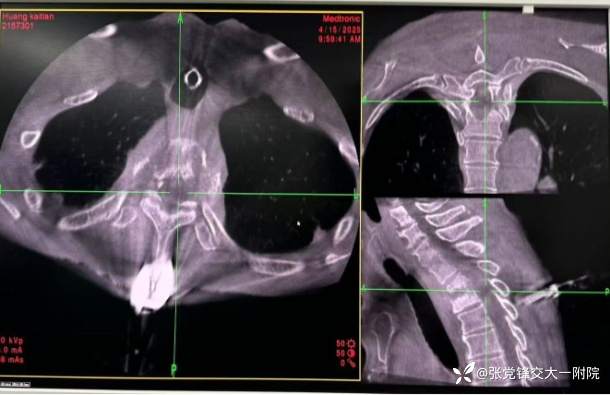

手术方案: O臂导航引导下经侧后方经皮椎间孔入路椎间孔镜下上胸椎结核病灶清除术

2.沿胸3棘突表面切开长约2cm切口,将棘突夹牢稳夹于胸3棘突, 安装导航参考架,使用0型臂三维影像系统扫描胸2-3椎间隙,获取三维重建图像,再次证实棘突夹子夹于胸3棘突上。

3.在导航引导下确定右侧穿刺点,选择侧后方肋横突间隙入路,避开肋骨头、穿刺点位于胸2棘突右侧旁开 3-4cm位置, 沿穿刺点切开皮肤 1cm, 导航实时引导下以 20G细针穿刺至胸2-3椎间隙右后外侧缘方向,导航三维显示在矢状位、横断位、冠状位上穿刺针位置良好,避免偏外损伤胸膜或偏内进入椎管损伤神经,导航引导沿穿刺针置入工作通道,过程中轻柔分离软组织,避免损伤神经血管束,避免穿透胸膜,连接椎间孔镜系统,生理盐水持续灌注。导航引导下沿正确方向逐渐将工作通道旋转打入胸2-3椎间隙后外侧缘,清除通道内此过程扩张脱落的少量骨性组织,进入病变区域,可见椎间隙后方有干酪样坏死物、死骨及炎性组织,使用镜下血咬骨钳等清除这些病变组织,扩大减压至相邻椎体后缘,病变组织清除后可见椎间隙后方脊髓硬膜囊膨起,神经根显露,脊髓和神经根压迫明显解除,并可见首髓波动。

4.同法,于胸2棘突左侧旁开3-4cm, 0形臂导航实时引导下于胸 2-3左后外侧缘方向置入工作通道,依次清创椎间隙左后方结核病变组织,检查硬膜囊搏动良好,无神经根受压,病灶范围满意,套管轨迹良好,同样未穿透胸膜,无气胸征象,神经电生理监测无异常,退出工作通道,缝合切口。

植入通道

定位:O臂引导下标记胸2-3肋横关节旁入路点。

穿刺与通道建立:在O臂导航下逐级扩张置入工作套管,避免穿破胸膜和损伤血管神经,对上关节突和椎弓根上缘成形。